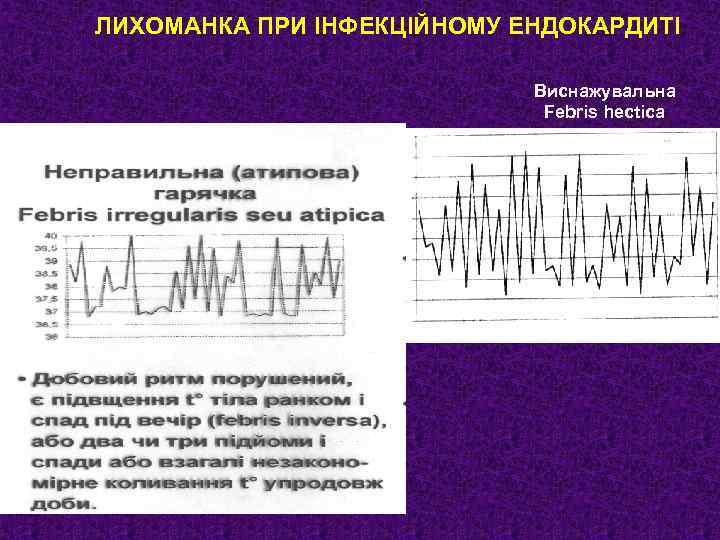

ЛИХОМАНКА ПРИ ІНФЕКЦІЙНОМУ ЕНДОКАРДИТІ Лихоманка- це терморегуляторне підвищення t° тіла як організована і координована відповідь організма на хворобу. Організм сам піднімає t° тіла вище, ніж вона є в нормі. Гіпертермія- це не лихоманка, а дисбаланс між теплопродукцією і тепловіддачею. t°С: 37° … 37, 9°С = субфебрилітет 38° … 39, 9°С = помірна лихоманка 40° … 40, 9°С = виражена лихоманка 41°С = гіперпірексія

ЛИХОМАНКА ПРИ ІНФЕКЦІЙНОМУ ЕНДОКАРДИТІ Виснажувальна Febris hectica